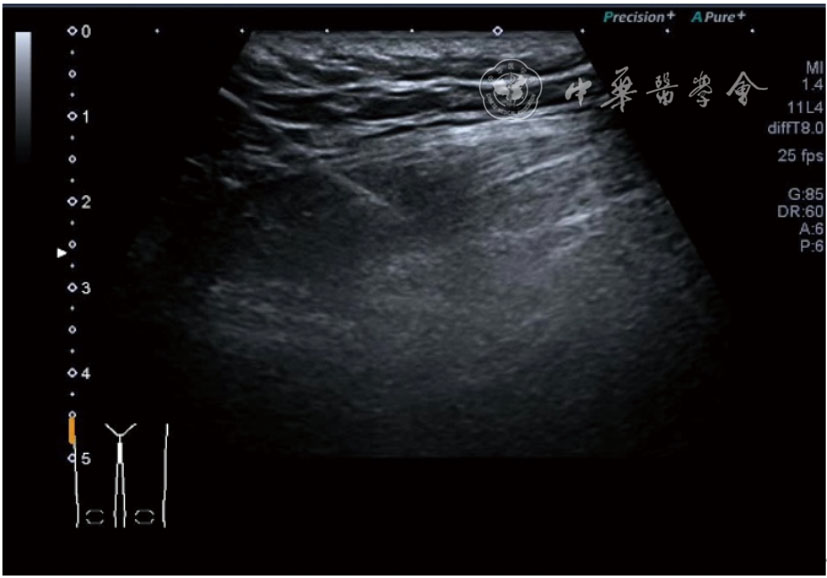

3.膝关节内局部治疗。随着病情发展,静态结构失衡,膝关节内部结构发生变化,会出现软骨损伤、脱落,关节间隙变窄,内外间隙不等,骨赘形成等。膝关节内局部治疗包括关节内症状性骨赘剥离、玻璃酸钠及PRP注射等。(1)膝关节内症状性骨赘针刀剥离松解治疗。由于软骨缺损或者力平衡失调,在关节内脱落软骨区会出现骨赘。部分骨赘引起疼痛,或者与髌骨撞击出现临床症状需要治疗。针刀剥离目的不是去除骨赘,而是剥离松解,缓解或者消除疼痛。以股骨外髁骨赘为例。患者平卧位,膝关节屈曲100°~120°。一般选用10 MHz超声探头,穿刺区域常规消毒,探头涂抹耦合剂后套入无菌手套碘伏消毒或使用无菌耦合剂。将探头置于患者皮肤表面,短轴扫查,显示关节面与骨赘,选用25G注射针,抽吸1%利多卡因3 ml于骨赘周围进行分层麻醉。选用直径1 mm的Ⅰ型2号针刀,在超声引导下从外侧向内侧到达骨赘,反复剥离,一般5~8刀后拔出针刀结束治疗(图18),局部压迫5分钟,无菌敷料覆盖。(2)膝关节髌上囊积液治疗。髌上囊积液在膝关节骨关节炎比较常见,尽管积液量可能很大,但通过软组织松解治疗后,大部分患者积液会减少或者消失。所以积液的治疗可以放在后面处理。超声引导下抽出积液,药物注射是常用的治疗方法。膝关节炎积液的治疗通常包括关节内皮质类固醇激素或者臭氧注射。如果慢性以滑膜丛型增生为主,针刀有限切割增生滑膜加药物注射可提高疗效。①髌上囊积液抽吸加臭氧注射治疗。患者平卧位,膝关节屈曲30°~60°,膝下垫一软枕。选用10 MHz超声探头,治疗前消毒准备同骨赘针刀剥离松解治疗。将探头置于患者皮肤表面,短轴扫查,找到积液最多处,应用22G针头,直接穿刺进入髌上囊抽出液体,然后根据髌上囊大小制备35 μg/L的15~20 ml臭氧注入髌上囊内拔出针头(图19),局部压迫2分钟,无菌敷料覆盖。②髌上囊慢性滑膜炎针刀切割松解治疗。患者平卧位,膝关节屈曲30°~60°,膝下垫一软枕。选用10 MHz超声探头,治疗前消毒准备同骨赘针刀剥离松解治疗。将探头置于患者皮肤表面,长轴或短轴扫查,找到积液最多处,用一次性5 ml注射器抽吸1%利多卡因3 ml于髌上囊进行分层注射麻醉,囊内也要注射适量麻药,尽量抽出积液。选用直径1 mm的Ⅰ型2号针刀,长轴扫查从近端向远端,短轴扫查从外侧向内侧,在超声引导下进入囊肿内对内壁及增生滑膜的不同方向、角度进行反复切割(图20),一般2~3分钟拔出针刀,然后囊内注射1%利多卡因3 ml+曲安奈德15 mg,结束治疗,局部压迫5分钟,无菌敷料覆盖。(3)膝关节腔PRP注射治疗。关节腔注射主要是为了修复软骨,如果不是为了治疗积液,不主张应用激素类药物。目前主要的注射药物为玻璃酸钠、PRP。按照传统的注射部位,多为髌上内、外或者髌下内、外注射点,但是超声不能观察到注射针的位置,药物也不能很好到达软骨损伤的部位,效果受到影响(图21)。膝关节软骨损伤的主要部位在髌股关节的股骨髁,超声可以很好地显示这一部位,并能显示软骨变薄。因此,由这个路径平面内进针注射,可以很好显示穿刺针的路径与位置。以注射PRP为例。患者平卧位,膝关节屈曲100°~120°,选用10 MHz超声探头,治疗前消毒准备同骨赘针刀剥离松解治疗。将探头置于患者皮肤表面,短轴扫查显示关节面,应用25G注射针头,抽吸1%利多卡因2 ml由内侧进针进行分层麻醉直达关节软骨面。制备4.5 ml PRP,直接注射到关节面,液体顺关节面分布,注射完毕拔出针头(图22)。局部压迫2分钟,无菌敷料覆盖。(4)髌骨软化超声影像融合技术下PRP注射治疗。髌骨软化是指髌骨关节面的软骨损伤,软骨下骨囊变,MRI能够明确诊断,但是超声不能显示。应用超声与MRI的影像融合技术,依据MRI明确注射部位,在超声引导下可将药物精准注射到软骨损伤的部位。患者平卧位,膝关节屈曲30°,下面垫一软枕。一般选用10 MHz超声探头,治疗前消毒准备同骨赘针刀剥离松解治疗。将MRI的原始图像数据导入超声设备中,进行手动影像融合,完全融合后,确定穿刺靶点,以MRI图像为目标,以超声图像为实时引导进行穿刺,到达目标后,注射提前制取的PRP 3 ml(图23),注射完毕拔出针头,局部压迫3分钟,创可贴覆盖。

图21 传统膝关节注射方法超声图像